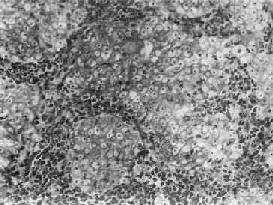

(3)泡状核细胞巢不规则,境界不甚明显,细胞胞浆丰富,境界不清晰,往往呈合体状聚集成堆。核大呈空泡状,圆形或卵圆形,有1~2个肥大的核仁,核分裂像并不多见(图9-6)。细胞间常可见淋巴细胞浸润。电镜下,可观察到紧挨淋巴细胞的细胞胞膜和胞质有破坏现象,这可能是淋巴细胞对细胞免疫攻击的结果。

鼻咽泡状核细胞<a href=癌"/>

图9-6 鼻咽泡状核细胞

细胞境界不清,呈合体状,核大圆形,染色质少,呈空泡状,含1~2个肥大的核仁,细胞间有淋巴细胞浸润